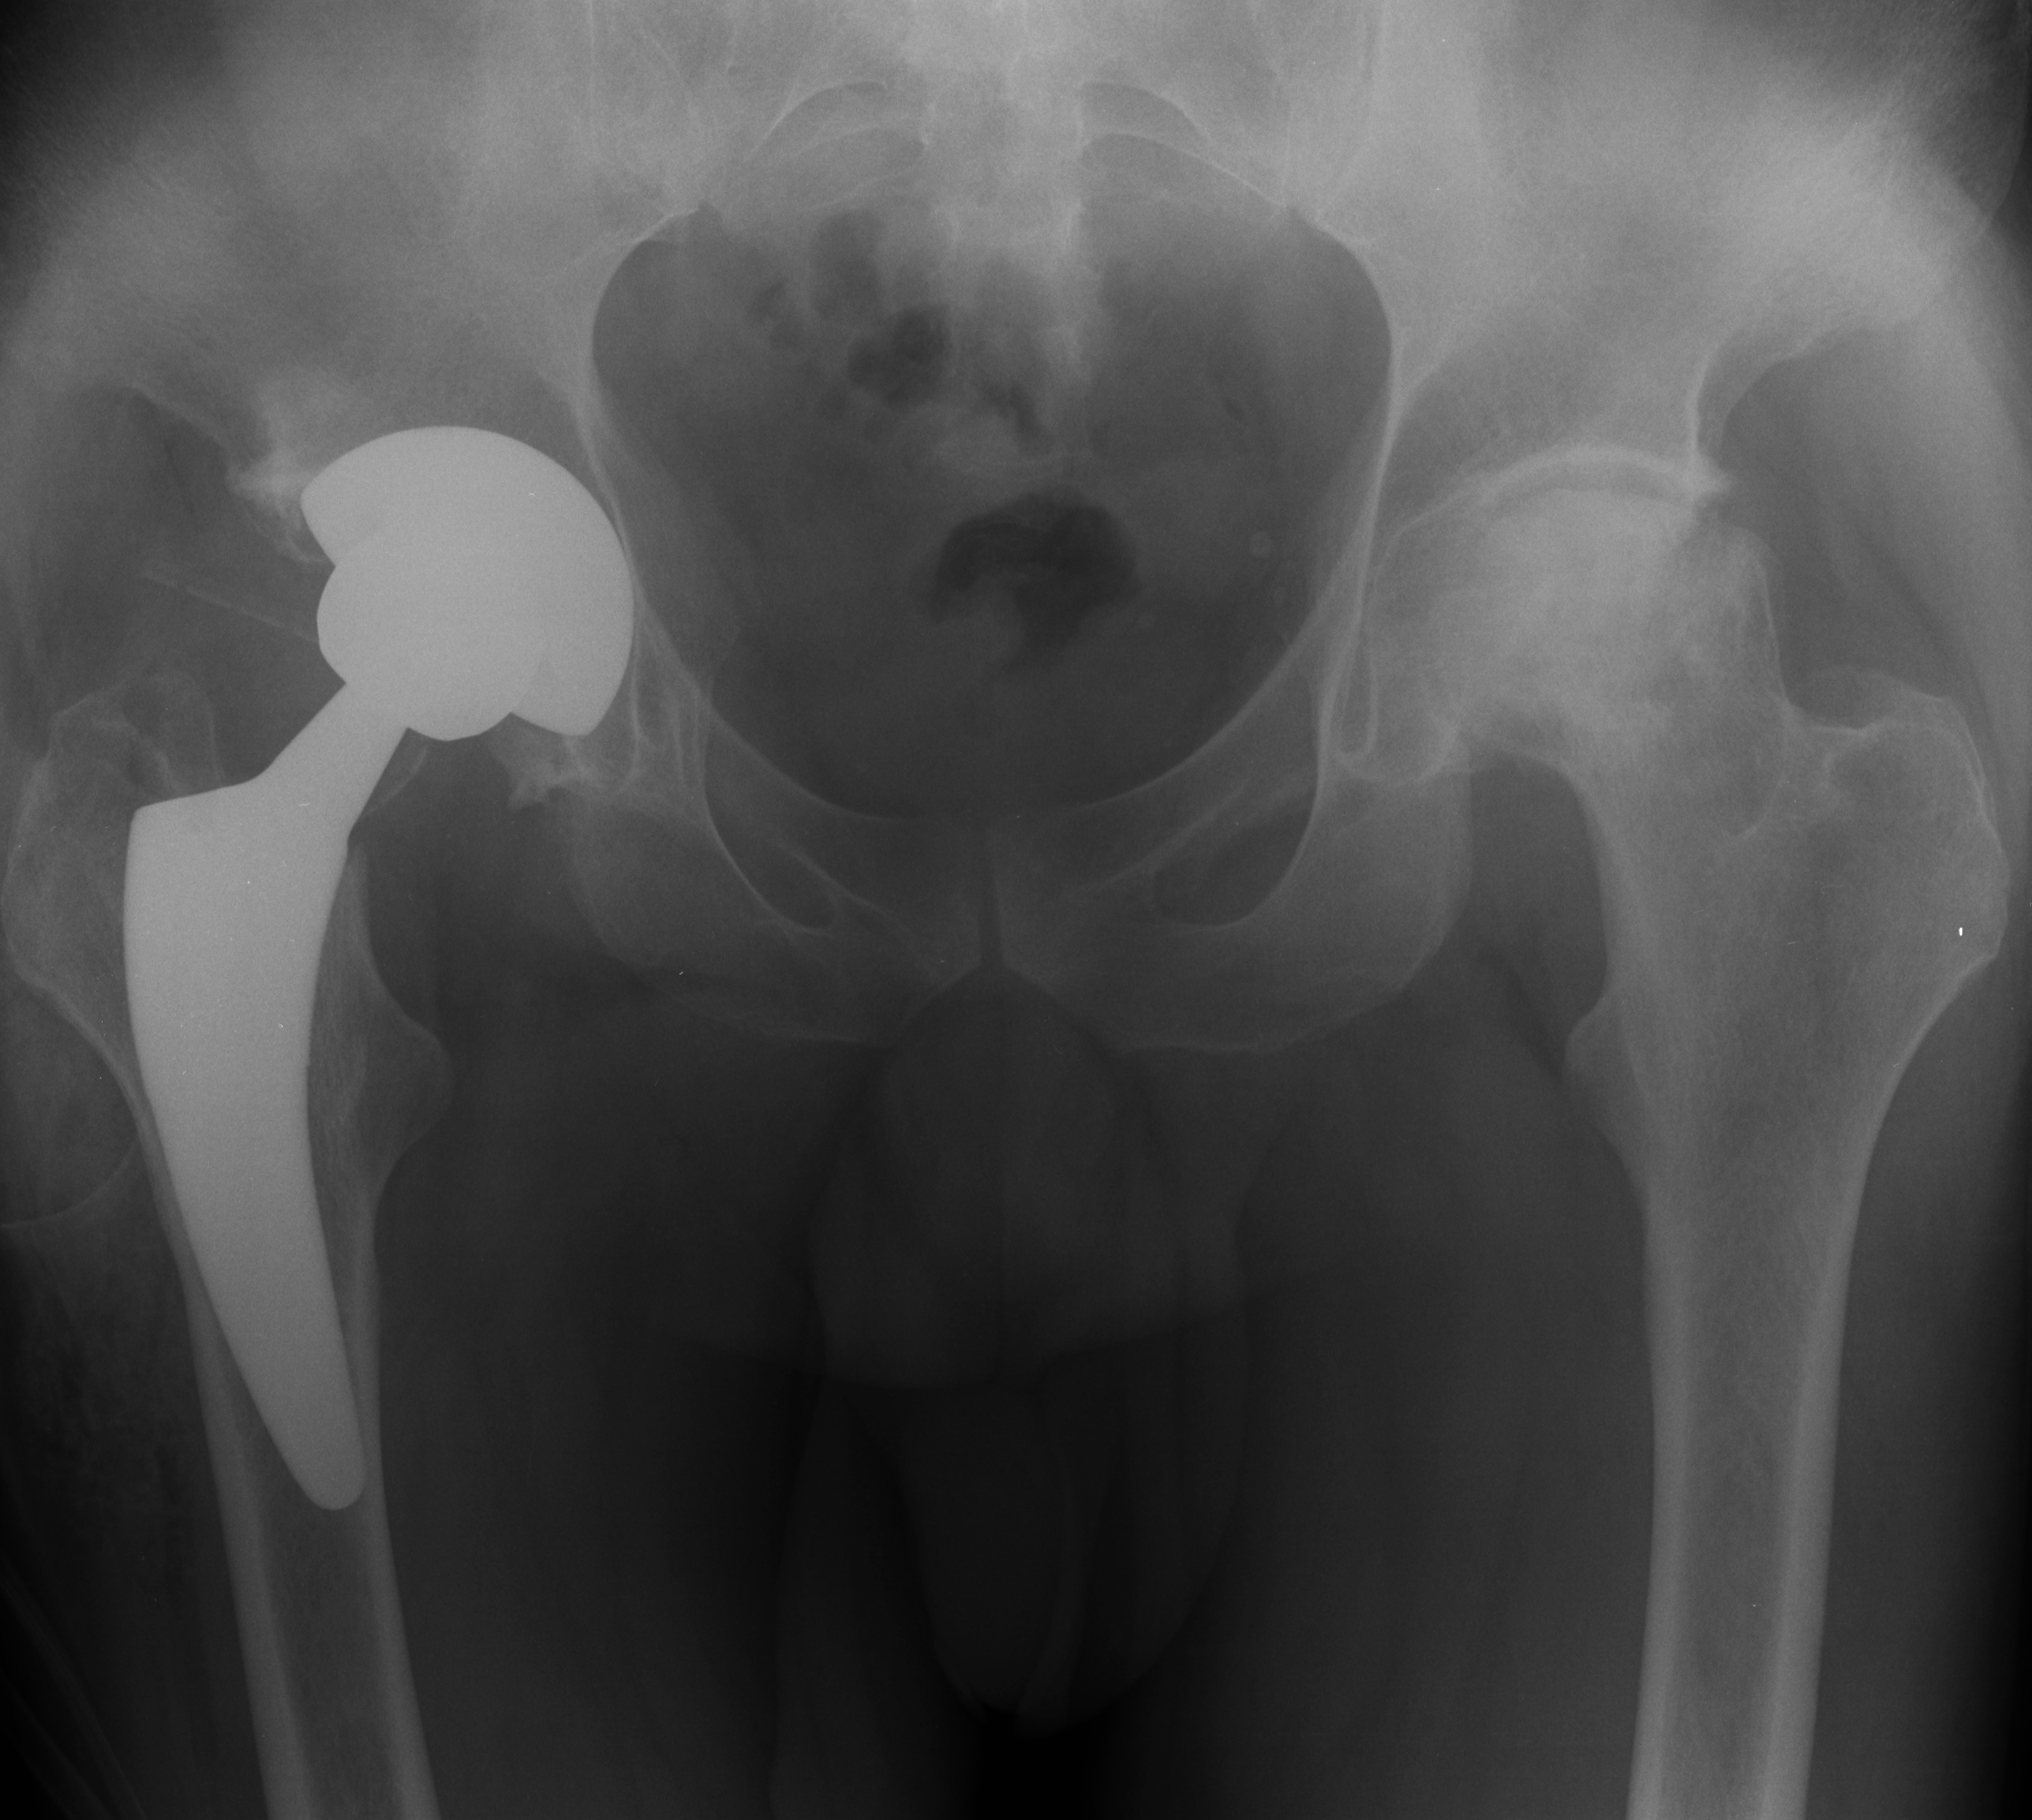

- Ендопротезиране на колянна и тазобедрена става

Основно лекувам заболявания на тазобедрена и колянна става чрез минимално инвазивно ендопротезиране, следтравматични и дегенеративни нарушения на ръката и китката и халукс валгус (популярен като „кокалчета на краката”).